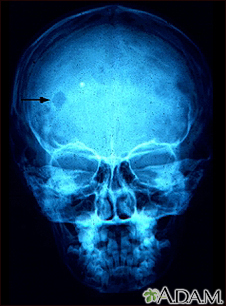

Eosinophilic granuloma - x-ray of the skull

This x-ray of the skull shows an eosinophilic granuloma (a lesion made-up of a type of white blood cell). This condition can range from a single eosinophilic granuloma to massive infiltration of skin, bone, and body organs.